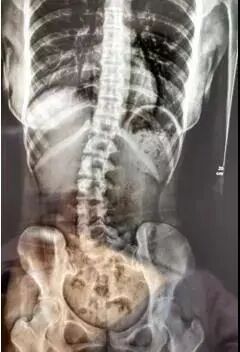

你能想象吗?这是一位16岁青少年的脊椎,它因疼痛而发生变形,侧弯程度严重到肉眼可见。

据接诊的医生说,小涛“来的时候,已经有了非常明显的代偿性脊柱侧弯”。

原来,小涛平时因为上课经常久坐,晚上也常常熬夜,“长期的久坐导致腰椎间盘已经有了损伤,埋下隐患,再加上打篮球这样的剧烈运动所产生的外力,从而诱发了疾病。”